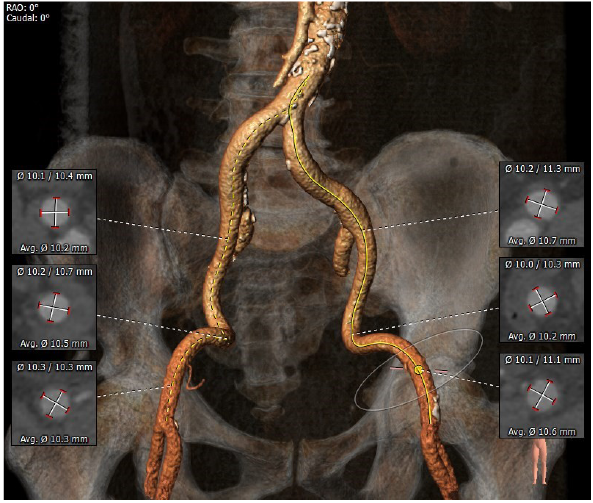

入路粗稍弯曲

4. 入路情况:入路直径较粗,稍弯曲,右股作为主入路

5.其他风险:心脏角度偏横位心,升主增宽,增加过弓难度,置入输送器时可调整超硬导丝调整方向延小弯侧方向靠。心尖较薄注意超硬导丝塑形防止心尖穿孔。